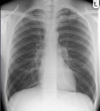

Normal CXR